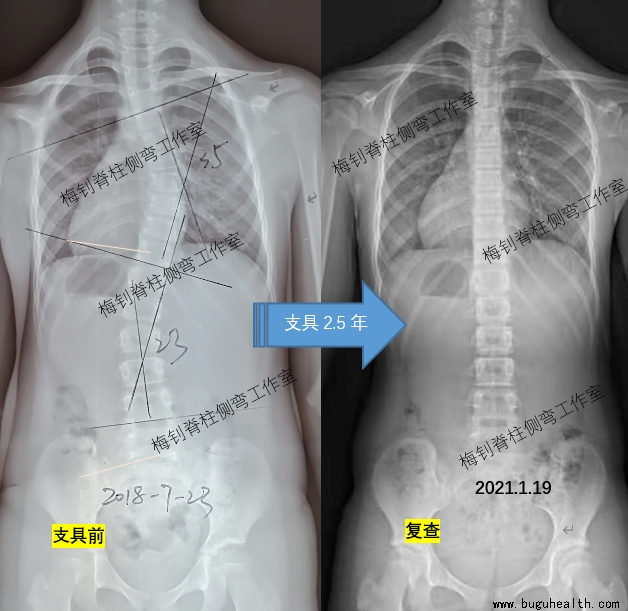

以下患儿,10岁发现侧弯,穿戴支具2.5年,脱支具48小时后拍片,脊柱保持竖直。开始减少穿戴时间,为脱支具做准备。

布骨康复医疗中心